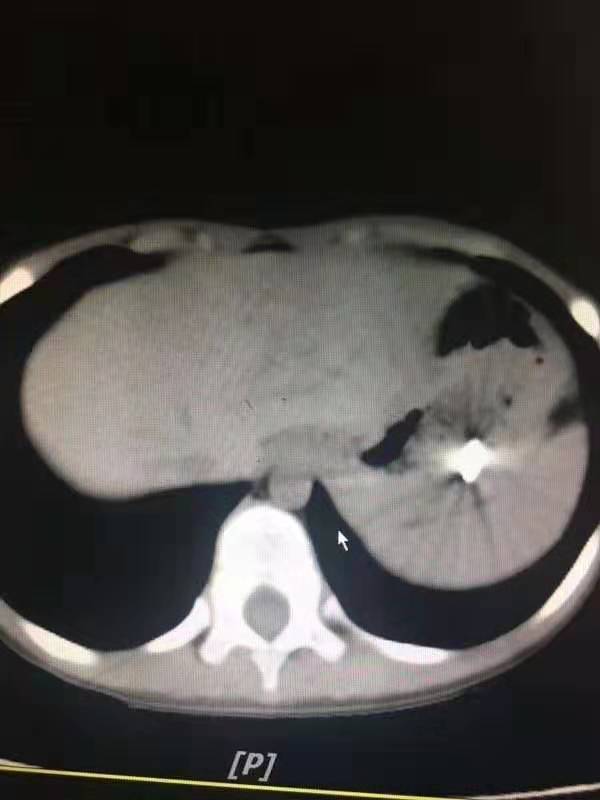

是采取胃镜探查还是腹腔镜探查?刘超医生带着刚刚办好住院手续的孩子做了x线片和CT,还好,钢钉还在孩子的胃里,胃壁没有穿孔。

19:40,孩子被推进了手术室,可胃镜下的一幕又让医生们吃了一惊,明明CT上显示钢钉在胃里,可是胃镜下的胃里空无一物。

医生们继续向下寻找,终于在十二指肠球部和降部交界的地方发现了卡住的钢钉。钢钉的尖端已经刺入了十二指肠球部的粘膜,这后面就是重要的大血管,一旦钢钉刺穿肠壁和血管后果不堪设想。